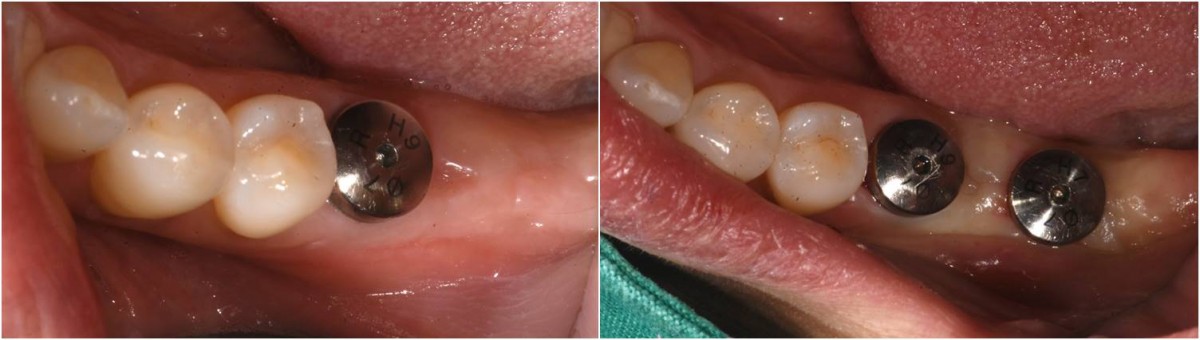

▲post-op panoramic radiograph.

▲. Panoramic radiograph after implant placement in the maxilla.(3 weeks after implant placement in the mandible)